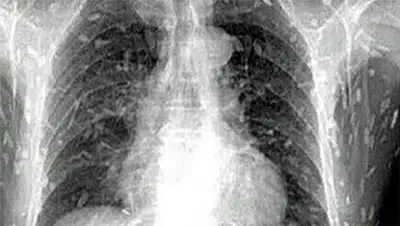

Шокирующие рентгеновские снимки организма мужчины, сделанные врачами одной из местных клиник, быстро разлетелись по Сети. На них видно, что буквально все тело любителя японских деликатесов напичкано жуткими паразитами.